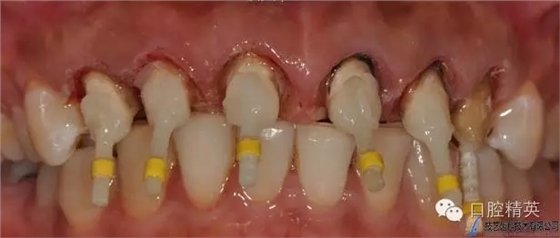

根管預備

PD纖維樁樹脂修復